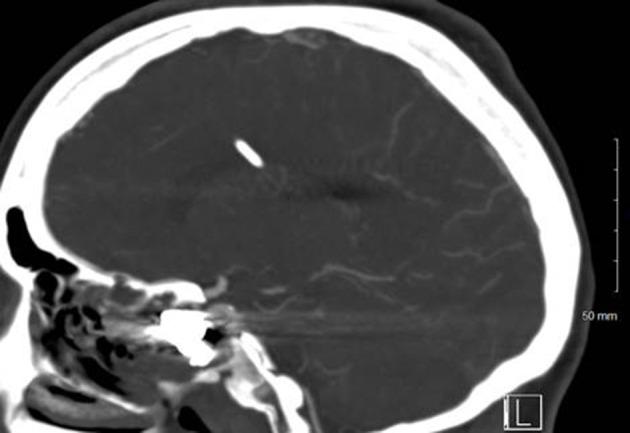

A 24-year-old female with history of traumatic brain injury with associated skull fractures due to a gunshot wound to the head 6 months prior presented to the ED in hemorrhagic shock secondary to epistaxis. After stabilization with the administration of blood products, Computed Tomography with Angiography (CTA) imaging of the head and neck was obtained and revealed a 3.1 × 2.2 × 2.5 cm pseudoaneurysm of the cavernous portion of the right internal carotid artery penetrating through the base of the skull into the ethmoidal sinus. The patient was taken for formal angiography by interventional radiology-and a partially thrombosed daughter sac of the initial aneurysm was identified and believed to be the source of the hemorrhage. The aneurysm was successfully coiled and occluded using ONYX embolization. Postoperatively, the patient returned to her baseline mental status without any acute complaints. The patient was discharged back to her nursing home 2 days later with a 3-week follow-up CTA revealing persistent occlusion of the aneurysm and a patent internal carotid artery.

一名24岁女性,6个月前因头部枪伤导致创伤性脑损伤并伴有颅骨骨折,因鼻出血继发失血性休克被送往急诊科。在输注血液制品使其病情稳定后,对头颈部进行了计算机断层血管造影(CTA)成像检查,结果显示右侧颈内动脉海绵窦段有一个3.1×2.2×2.5厘米的假性动脉瘤,该动脉瘤穿过颅底进入筛窦。患者被介入放射科送去进行正式血管造影,发现了最初动脉瘤的一个部分血栓形成的子囊,并认为这是出血源。使用Onyx栓塞剂成功地对动脉瘤进行了弹簧圈栓塞和封堵。术后,患者恢复到基线精神状态,无任何急性不适主诉。患者于两天后出院回到养老院,3周后的CTA随访显示动脉瘤持续闭塞,颈内动脉通畅。